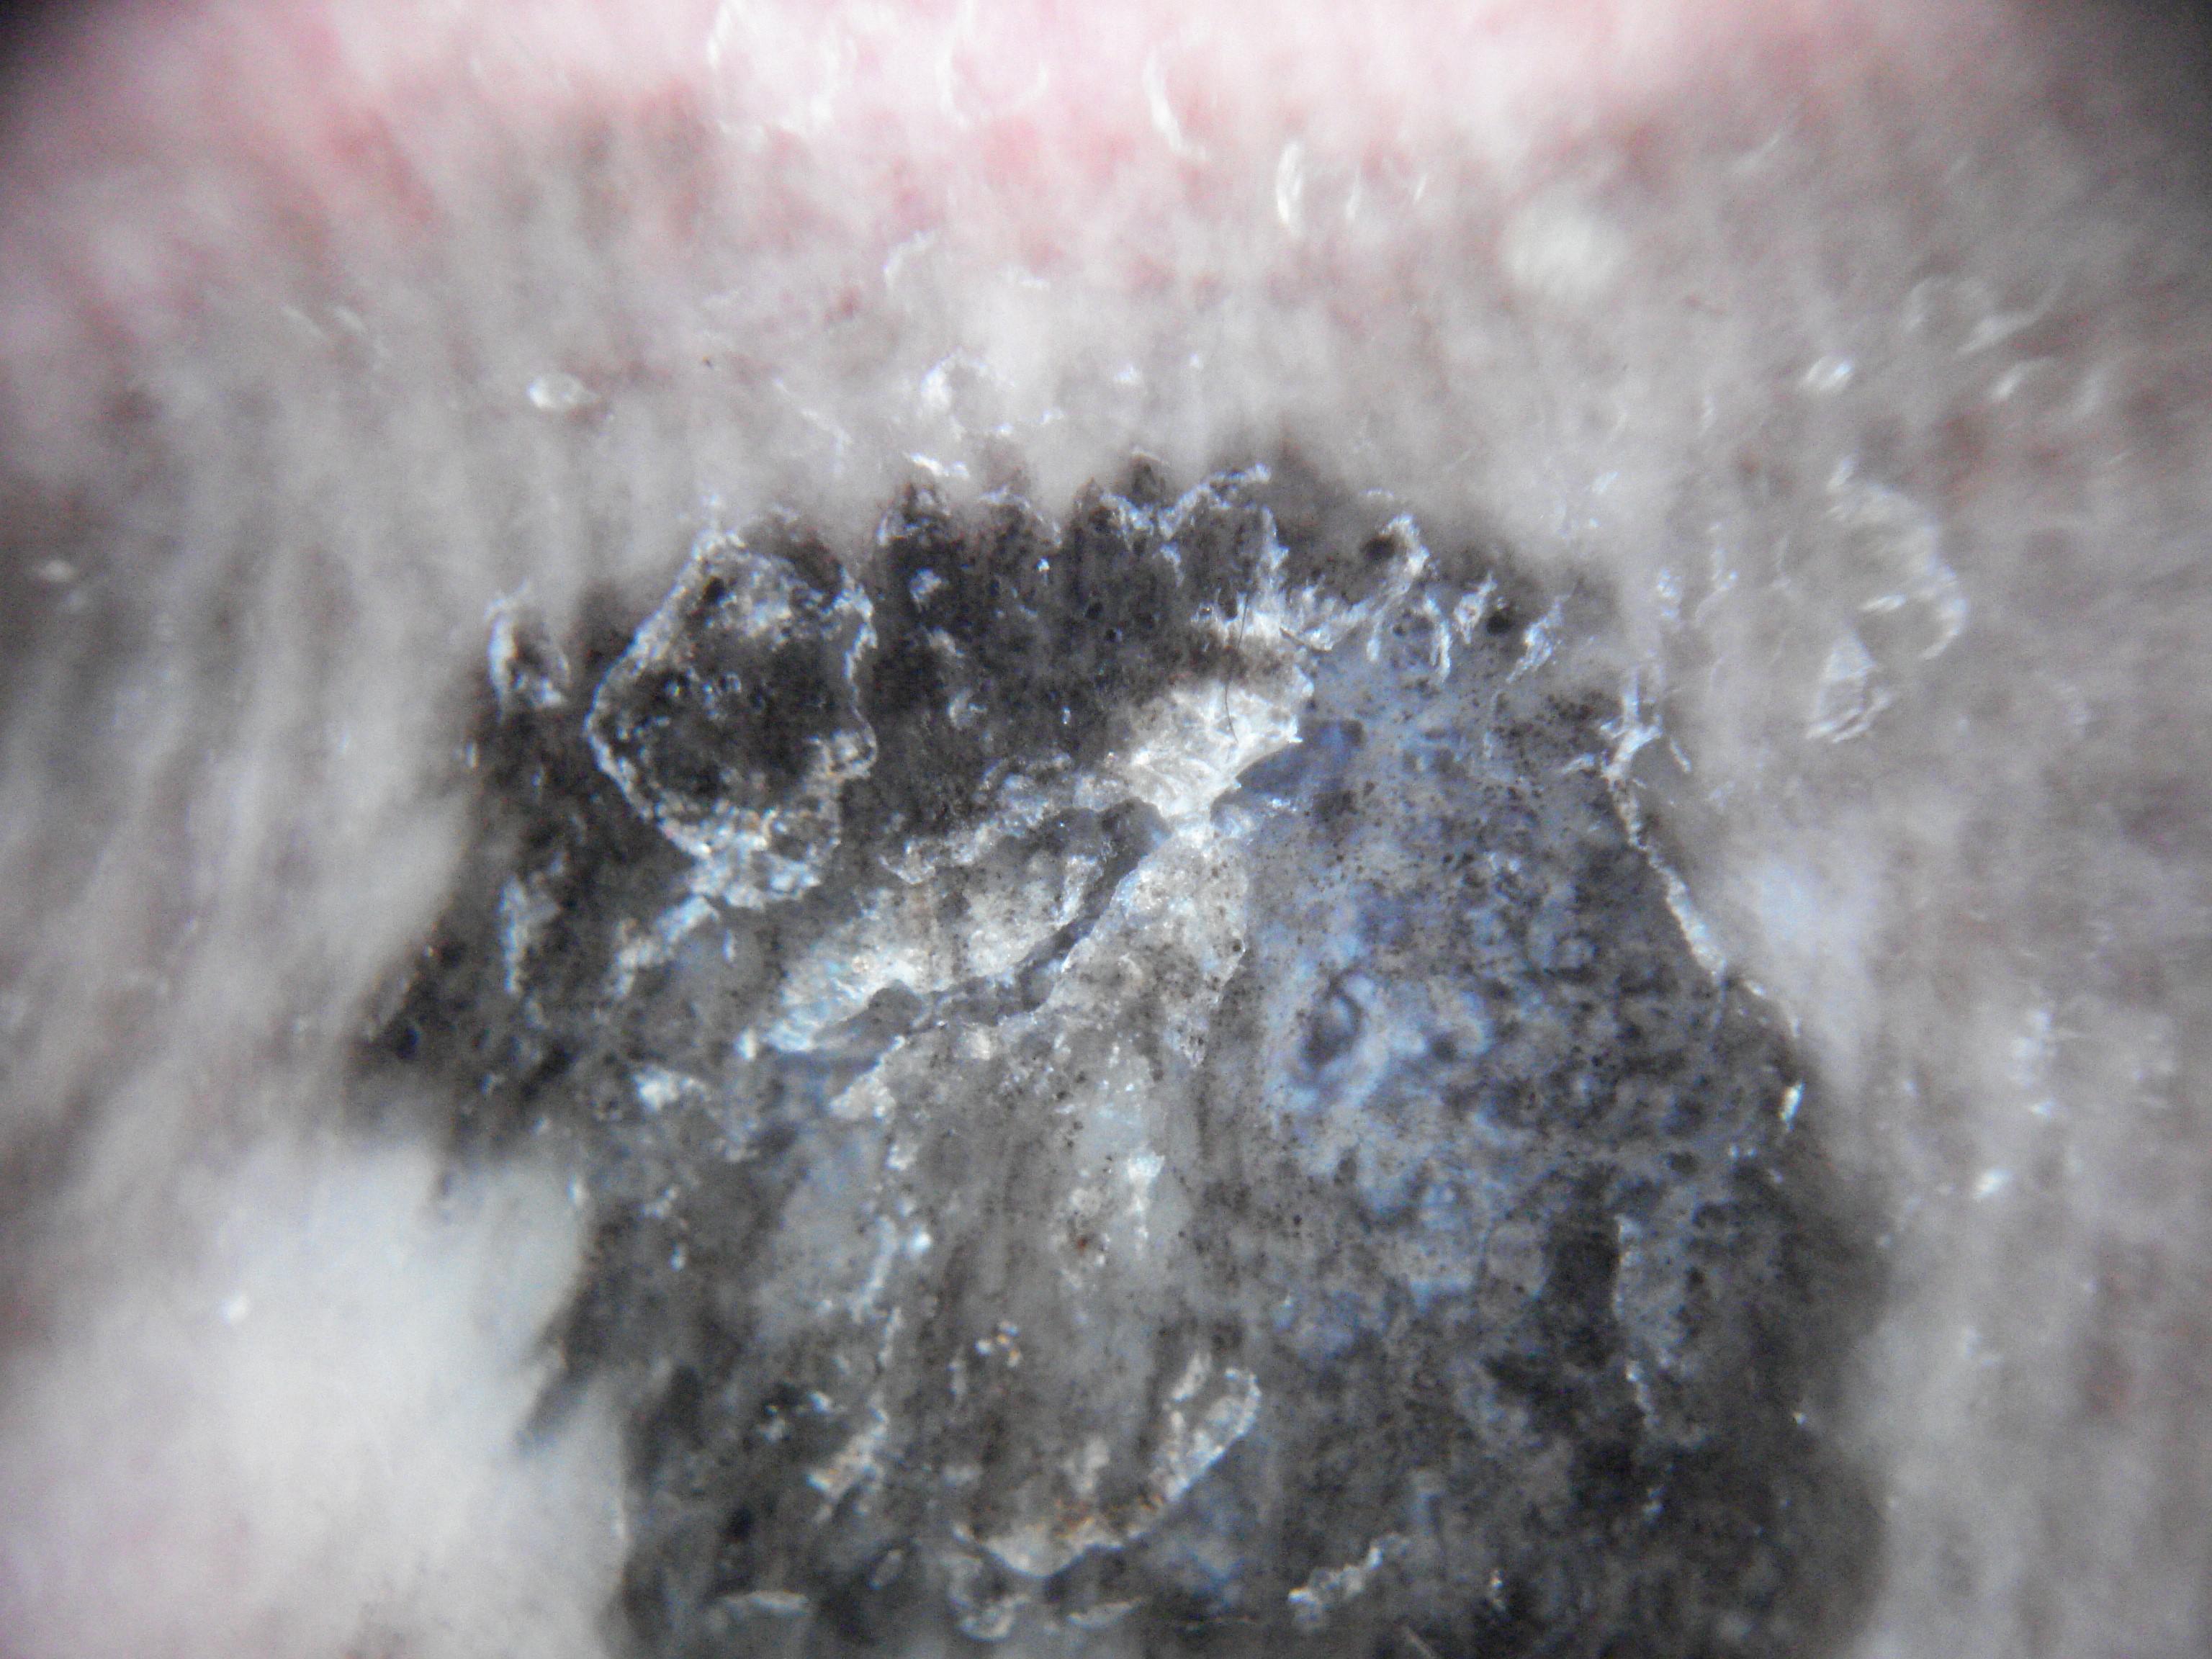

{

"age_approx": 85,

"anatom_site_general": "lower extremity",

"concomitant_biopsy": true,

"dermoscopic_type": "contact non-polarized",

"diagnosis_1": "Malignant",

"diagnosis_2": "Malignant adnexal epithelial proliferations - Follicular",

"diagnosis_3": "Basal cell carcinoma",

"diagnosis_confirm_type": "histopathology",

"family_hx_mm": false,

"image_type": "dermoscopic",

"melanocytic": false,

"patient_id": "IP_1166087",

"personal_hx_mm": true,

"sex": "female"

}